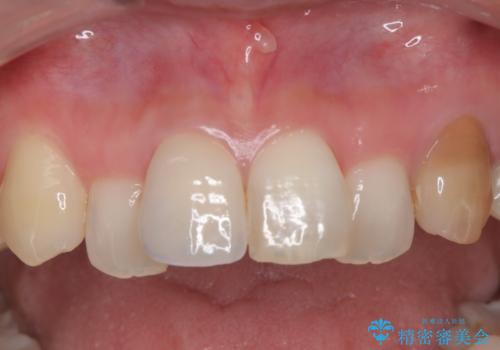

汚れた仮歯が気になる 前歯のオールセラミッククラウン

【オールセラミック】前歯の色を変えたい。

見栄えの悪い仮歯 前歯のオールセラミック治療